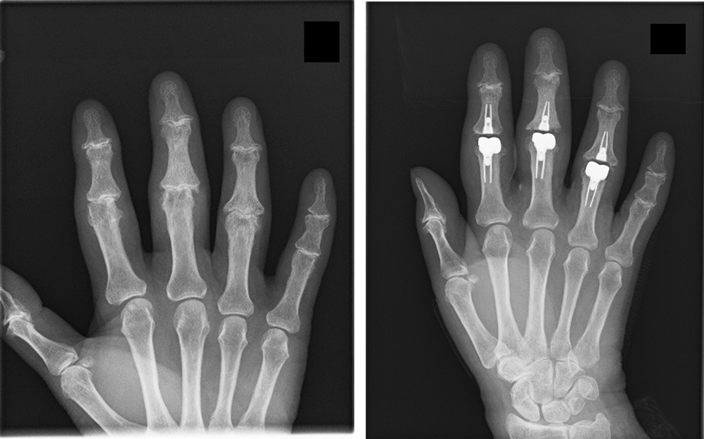

上肢は体重など大きな力が加わらないため、膝や股関節と比較して変形性関節症の発生頻度は少ないですが一定の割合で発生しています。肩の腱板が断裂した状態が長期経過し変形性肩関節症を併発する患者様や加齢に伴い肘関節や指のPIP関節(第2関節)・MP関節(第3関節)の変形性関節症を発生する患者様おられます。人工肩関節置換術、人工肘関節置換術、人工指関節置換術を行うことで除痛と可動域獲得の手術も行っています。

※2024年現在DIP関節(第1関節)は適切な人工関節がないため関節固定を行っています。